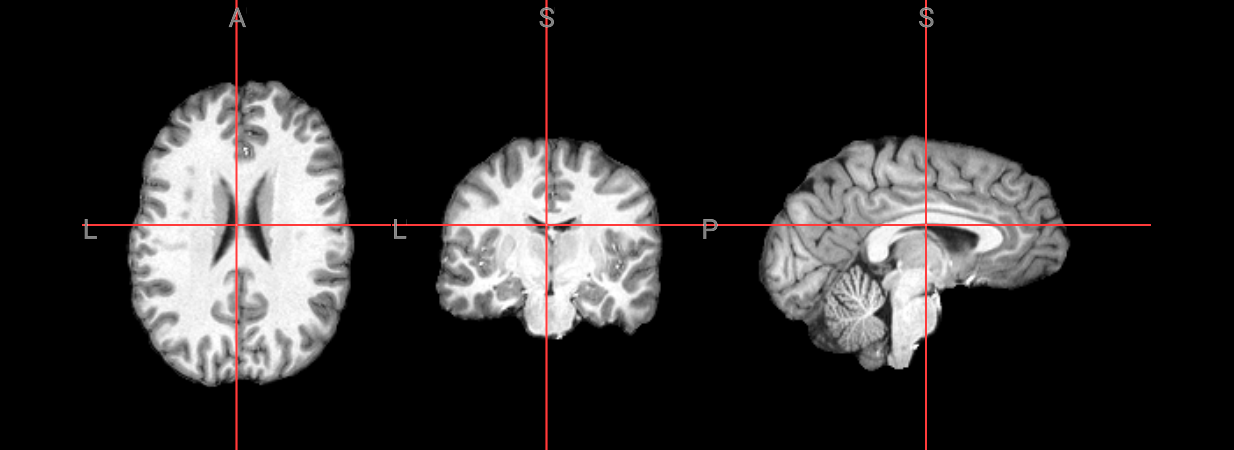

Since fMRI studies focus on brain tissue, our first step is to remove the skull and non-brain areas from the image.

T1 Image for brain extraction#

input_image = 'ds000102/sub-08/anat/sub-08_T1w.nii.gz'